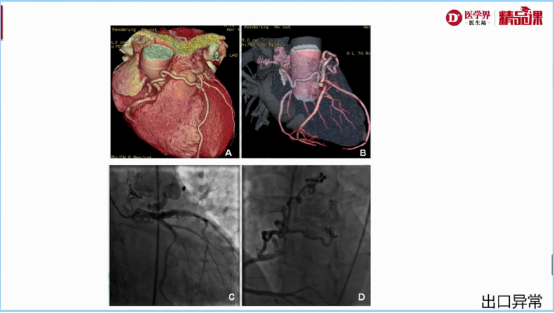

1.容积重建(VR):冠脉立体结构,只看冠脉起源、走形,不看狭窄

图3:容积重建冠脉走形异常举例

图4:容积重建冠脉出口异常举例